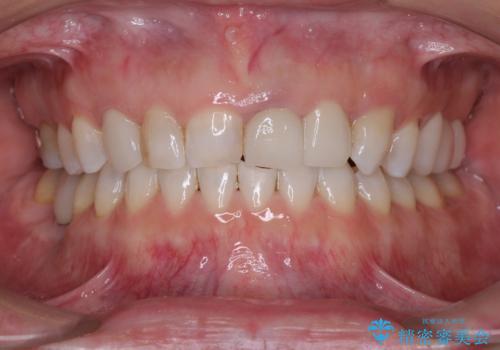

- 前歯の出っ歯と口元の閉じにくさを気にして来院された患者様です。

口元を積極的に引っ込めるために、上下左右の小臼歯4本を抜歯することとしました。

4本の歯を抜歯したことで、飛び出していた口元が引っ込み、横顔が大きく改善されました。

咬み合わせが悪化することのないようにスペースを閉じていくことができ、比較的スムーズに治療を進めることができました。